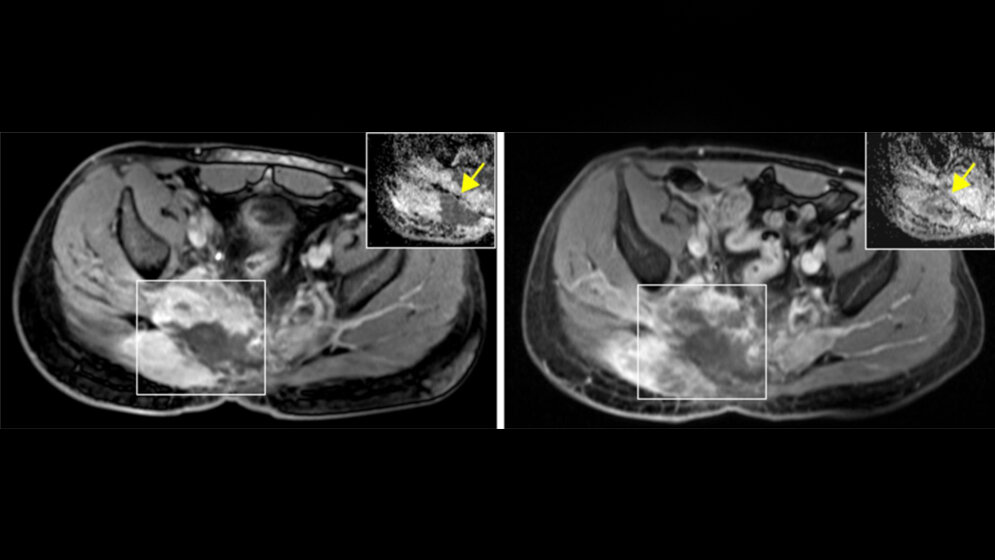

Da sich bei anderen Krebsarten, bei denen ebenfalls ein HR-Defizit vorliegt, bestimmte Arzneistoffe als wirksame Medikamente erwiesen haben, lag es nahe, diese auch bei Chordom-Patienten als weitere Behandlungsoption einzusetzen. Die Ärzte führten bei einem Betroffenen mit passendem genetischem Profil eine experimentelle Behandlung mit einem so genannten PARP-Inhibitor durch. PARP-Inhibitoren hemmen das Enzym Poly-ADP-Ribose-Polymerase (PARP) und verhindern dadurch, dass Krebszellen Schäden an ihrer DNA, die etwa in Folge einer Chemotherapie auftreten, wieder reparieren können. Bei dem behandelten Patienten führte die Gabe eines PARP-Inhibitors zu einer langanhaltenden klinischen Verbesserung und einem Stillstand des Tumorwachstums. Nach erneutem Fortschreiten der Erkrankung bei demselben Patienten konnte das Team um Stefan Fröhling, Stefan Gröschel und Robert Russell vom BioQuant Heidelberg eine neuartige Resistenzmutation des PARP1-Enzyms identifizieren, welche die Wirkung des PARP-Inhibitors aufhob.